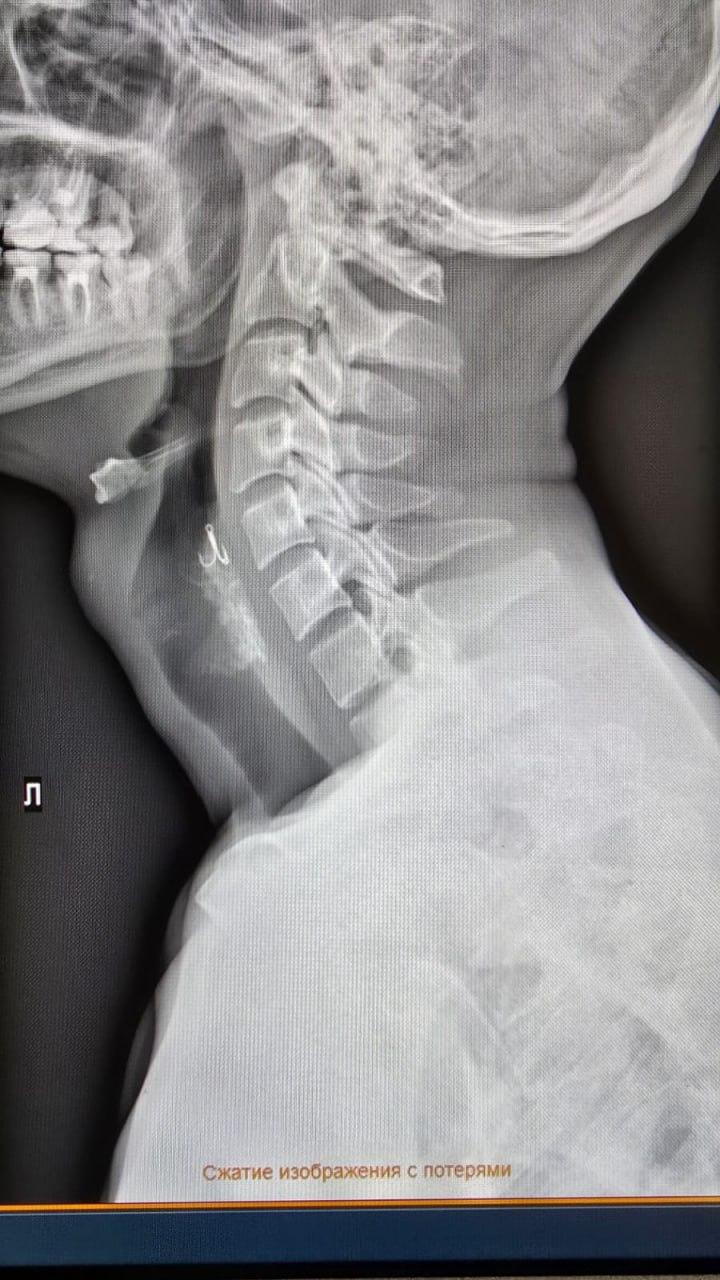

Житель Красноярска на рыбалке проглотил крючок

Мужчина держал во рту снасть, и когда лодку качнуло, случайно проглотил её. С острой болью он срочно обратился в больницу. Крючок застрял в горле. Врачи краевой больницы с помощью эндоскопа извлекли наживку.

Сейчас с мужчиной всё в порядке.